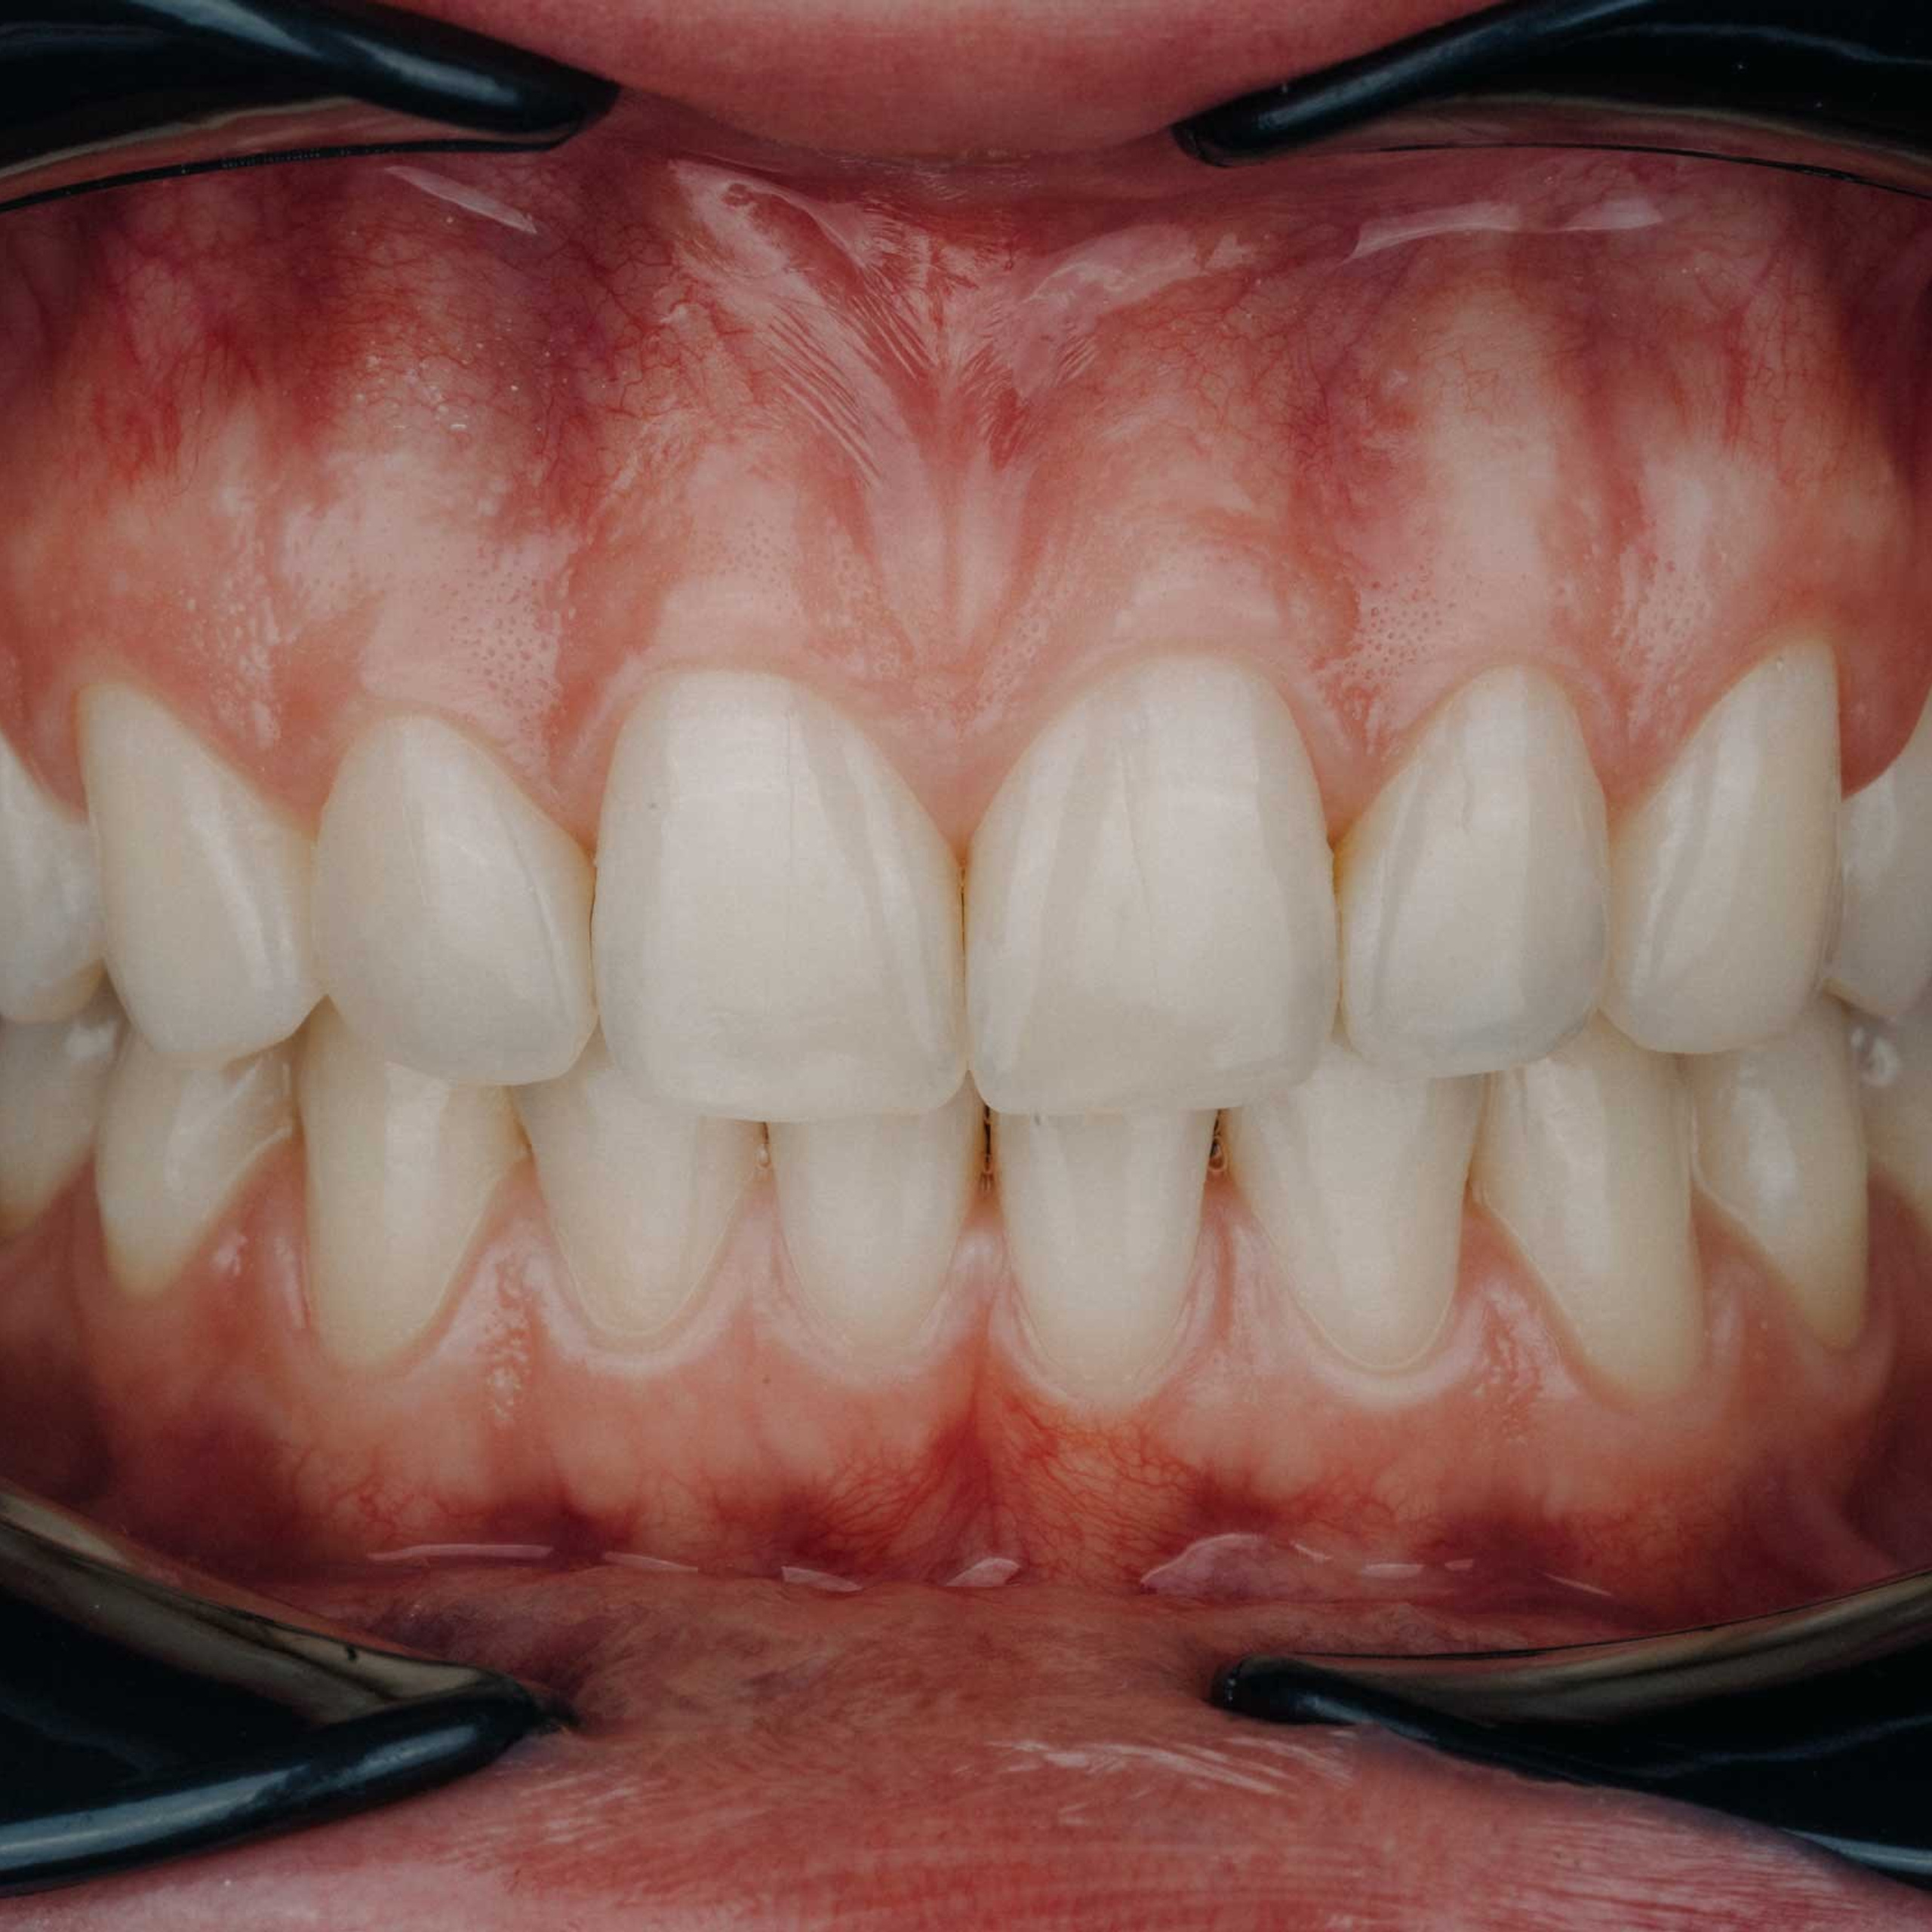

Фотографии учеников до обучения

Фотографии после обучения